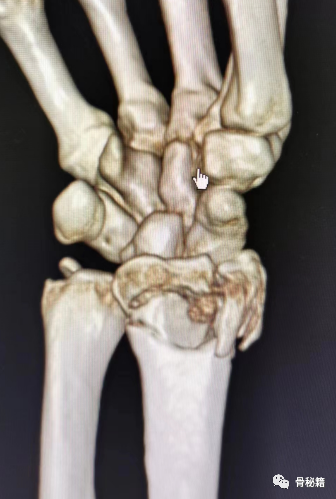

识别并开始使用最能稳定腕骨,以使其正常空间关系不稳定的碎片进行复位。月骨面掌侧边缘的复位、骨折,特别注意长度的恢复和泪滴型角度的校正,通常是治疗复杂关节损伤的关键。

还有一些相应的内固定设计,专门诊断此类边缘骨折

• 注意,需要对腕骨韧带损伤保持高度怀疑。考虑关节镜评估,特别是在桡骨或背侧剪切骨折、腕骨撕脱/不稳定模式或与舟骨和月骨面之间显着纵向台阶相关的关节骨折的情况下。